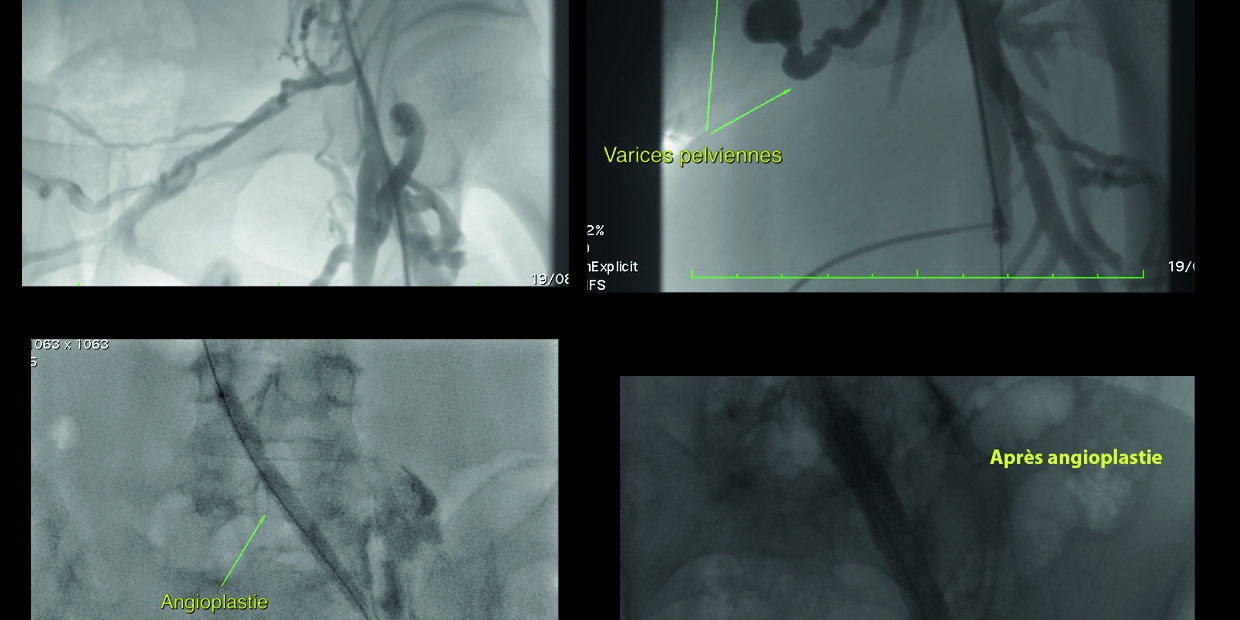

Après dilatation avec un ballonnet, le cardiologue interventionnel implante un ou plusieurs stents dans la veine obstruée permettant ainsi de rétablir le flux normal et de soulager les symptômes. (illustration par un cas d’occlusion de la fémorale commune jusqu’à l’iliaque avec nombreuses varices pelviennes qui disparaissent après les stents)